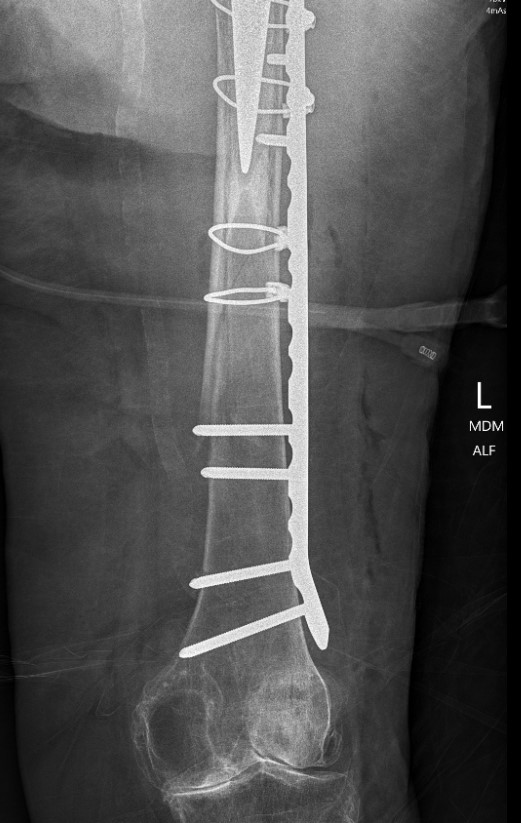

ORIF with locking cable plate and +/- Cortical strut allograft

Plates

Contoured anatomical fit with trochanteric extension

Variable angle locking screws to go around implants

Cable options

Unicortical screw options

Revision uncemented arthroplasty with Zimmer cable plate